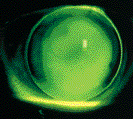

Microcycts, frequently seen with hydrogel extended wear,

are far less common with RGP extended wear.

Microcysts are tiny refractile lesions that are often described as bundles of cellular debris. They originate from the deep epithelial layers and eventually migrate to the corneal surface. Microcysts are generally an indicator of chronic corneal hypoxia or other metabolic disorders and are usually detected after several weeks or months of extended wear. Clinical trials have reported microcystic changes ranging from seven to 35 percent in enrolled subjects. This seems to support the need for frequent follow-up visits to detect which patients have higher corneal oxygen demands.